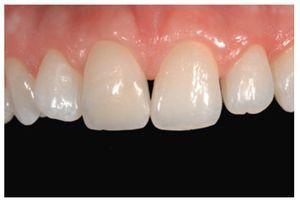

El pulido final es fundamental para el éxito estético de las restauraciones, ya que una superficie brillante y lisa reduce el acúmulo de placa y previene la decoloración de los dientes (Shiny System, Micerium). Al final, la restauración pulida presentaba una superficie muy similar a la del diente natural (figuras 49 y 50). No obstante, este nivel de resultado clínico obtenido con una técnica directa sólo es posible con un manejo correcto de la forma y la reconstrucción. Estos parámetros deben ser determinados antes de instaurar los procedimientos clínicos (figuras 51 y 52).

Figura 49 Vista de las restauraciones y los elementos rehidratados después de 72 horas.

Figura 50 Buena integración estética de las restauraciones y salud de los tejidos periodontales 30 días después del tratamiento.

Figura 52 Revisión a los dos años.